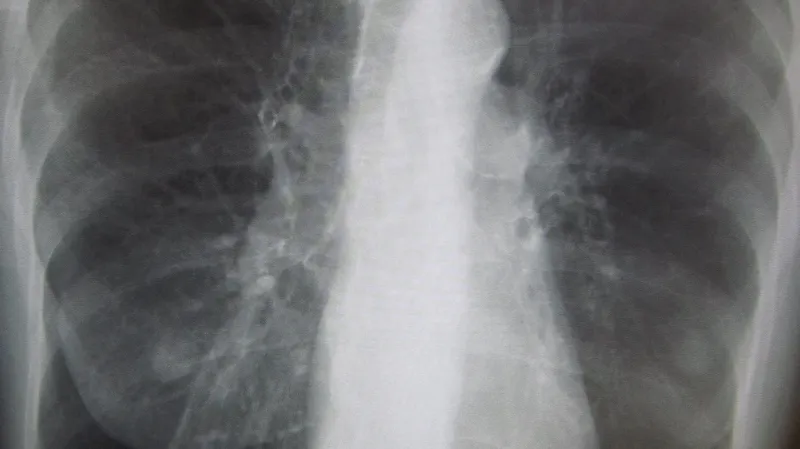

Nemoc je důsledkem chronického zánětu průdušek, který vede k jejich zužování a ke zvýšené tvorbě hlenu. Projevuje se zadýcháváním, chronickým kašlem a vykašláváním hlenu. Kromě kouření souvisí její výskyt se znečištěným prostředím, genetikou a opakovanými záněty dýchacích cest.

Pacienti v nejtěžších stadiích končívají na JIP s náhlým dechovým selháním, potřebují přístrojovou podporu dýchání. V domácí péči pak musejí dlouhodobě dostávat kyslík, u některých je řešením transplantace plic, které nemoc postupně zničí.